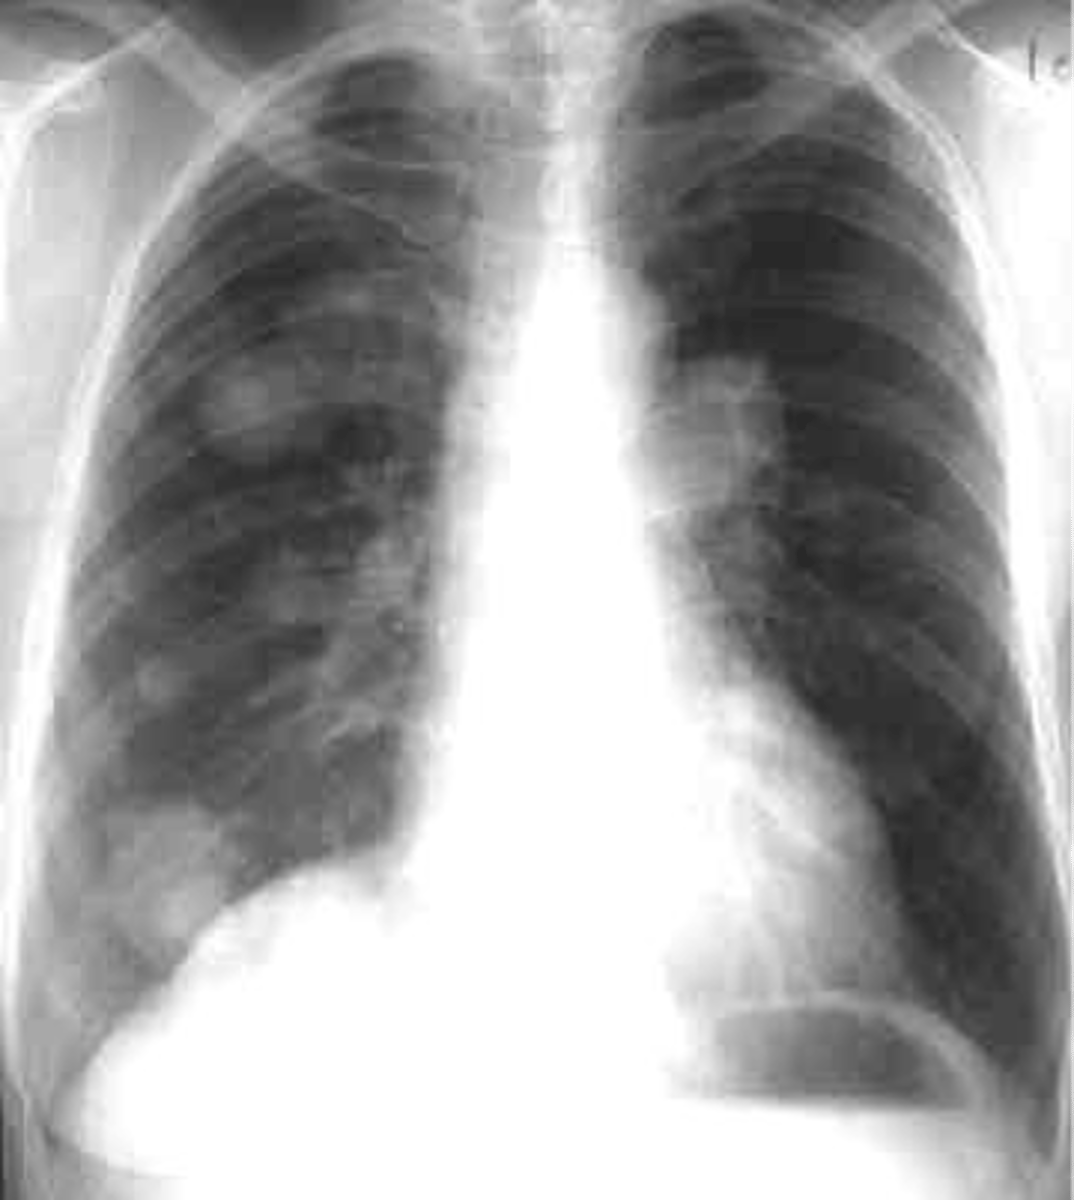

Multiple nodules- metastatic